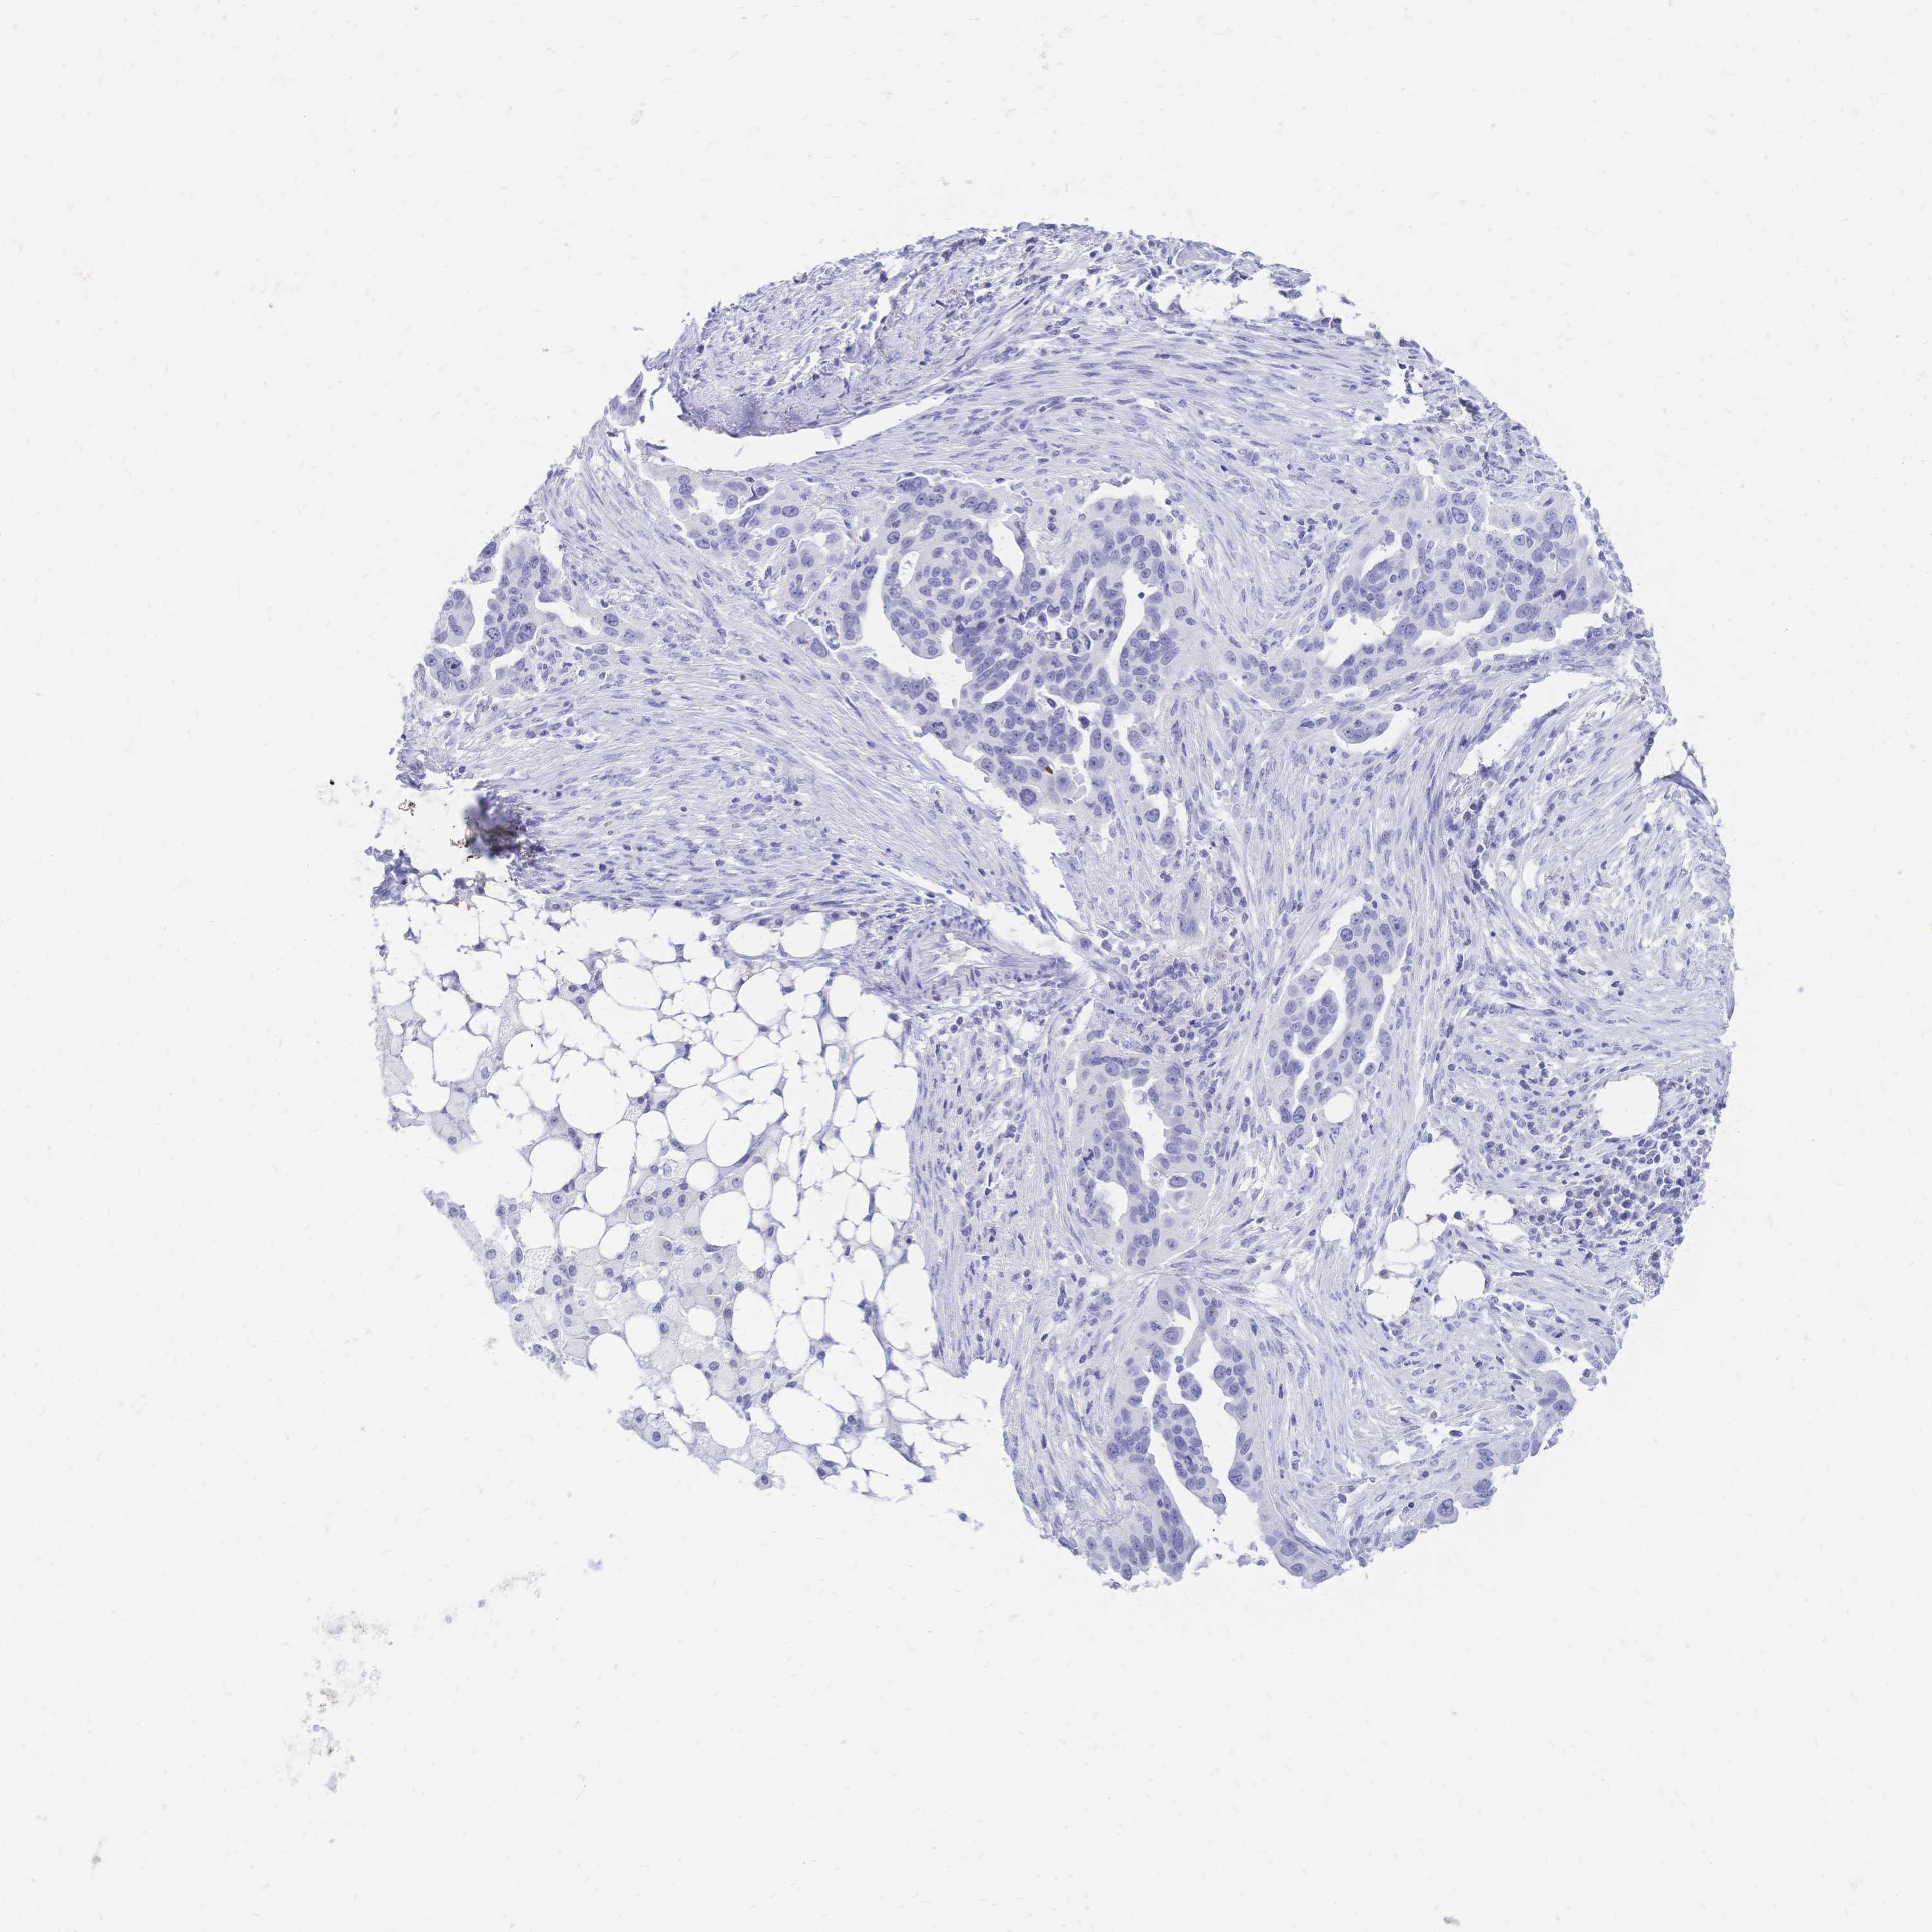

OVARIAN CANCER - Protein expressioni

A mouse-over function shows sample information and annotation data. Click on an image to view it in a full screen mode. Samples can be filtered based on level of antibody staining by selecting one or several of the following categories: high, medium, low and not detected. The assay and annotation is described here.

Note that samples used for immunohistochemistry by the Human Protein Atlas do not correspond to samples in the TCGA dataset.

Antibody stainingi

Antibody staining in the annotated cell types in the current human tissue is reported as not detected, low, medium, or high, based on conventional immunohistochemistry profiling in selected tissues. This score is based on the combination of the staining intensity and fraction of stained cells.

Each image is clickable and will lead to virtual microscopy that enables deeper exploration of all samples and also displays staining intensity scores, fraction scores and subcellular localization as well as patient and tissue information for each sample.

Antibody HPA056614

Staining

High

Medium

Low

Not detected

Intensity

Strong

Moderate

Weak

Negative

Quantity

>75%

75%-25%

<25%

None

Location

Nuclear

Cytoplasmic/membranous

Cytoplasmic/membranous,nuclear

Cystadenocarcinoma, serous, NOS

Cystadenocarcinoma, mucinous, NOS

Carcinoma, endometroid